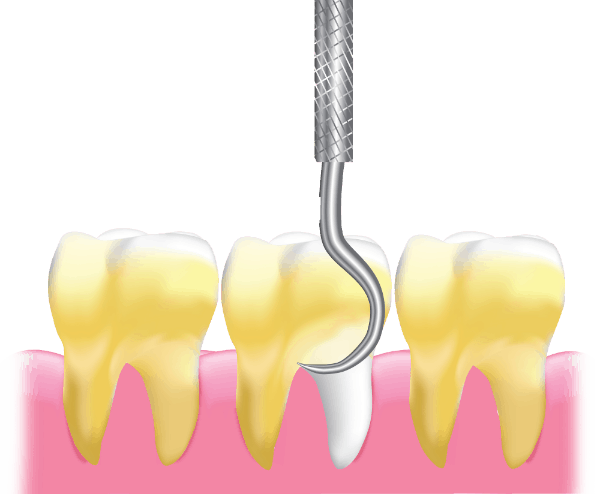

Scaling

Maintain optimal oral health with professional teeth scaling. Removes plaque, tartar, and stains, preventing gum disease and bad breath.